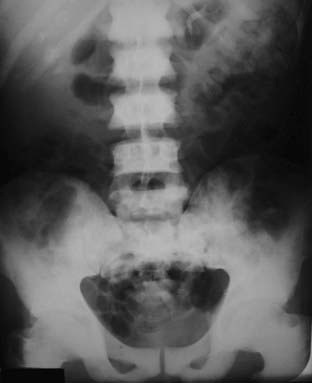

Figure 21-5 Osteopetrosis (marble bone disease).

A frontal view of the pelvis demonstrates diffuse sclerosis of the bones in this 22-year-old patient with osteopetrosis, a rare defect in osteoclastic activity that results in an increase in bone density. Although the bones are dense, they are mechanically inferior to normal bone and subject to pathologic fractures. In the infantile form of this disease, the defective osseous material can replace normal bone marrow leading to anemia, thrombocytopenia, and leukopenia (pancytopenia).